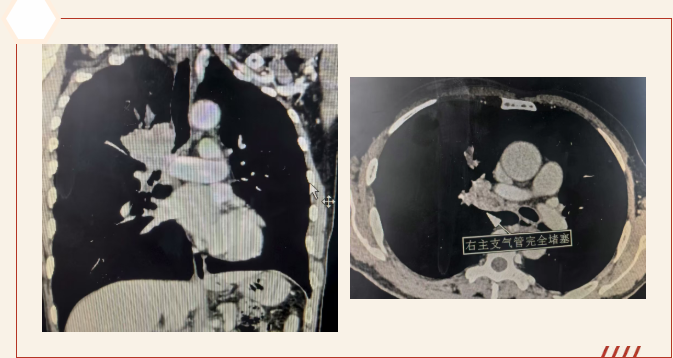

2个月前,此患者开始出现不明原因的呼吸困难,且症状逐渐加重。入院后完善检查,胸部 CT 显示右主支气管存在占位性病变;进一步支气管镜检查更明确 —— 右主支气管腔内被新生物完全阻塞,管腔狭窄程度竟达 90% 以上,右侧肺叶通气功能几近丧失。若不及时打通气道,不仅呼吸困难会持续加重,还可能引发肺部感染、呼吸衰竭等致命风险,更无法开展后续抗肿瘤治疗。